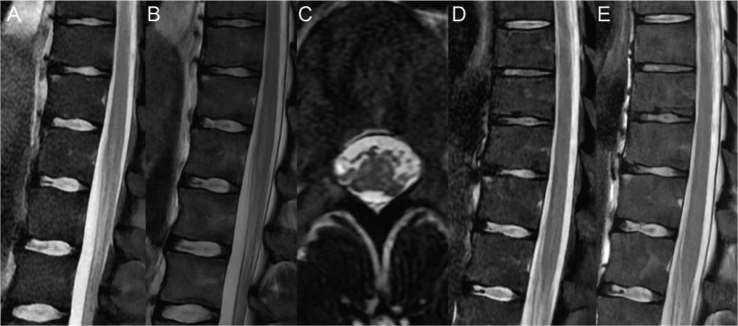

Results: Spinal cord imaging showed hyperintensities with a quadrifocal white matter involvement. Neurophysiological study revealed peripheral motor impairment.

目的:报告1例雷击后周围神经病变和脊髓损伤并发截瘫病例,强调影像学表现和神经生理学结果,以提高认识和治疗。设计:一份病例报告。患者:29岁男性,无明显病史或手术史,遭雷击。方法:进行神经学评估、脊髓成像、肌电图研究和体感诱发电位评估。影像学结果和周围神经评估比较现有文献雷电相关损伤。结果:脊髓成像显示高信号伴四灶性白质受累。神经生理学研究显示外周运动障碍。结论:本病例记录了雷击后中枢和周围神经系统损伤导致的截瘫。独特的脊髓成像结果和神经生理学研究有助于理解神经损伤机制。鉴于雷击频率的增加,这些发现可能有助于改进临床管理和患者教育策略。